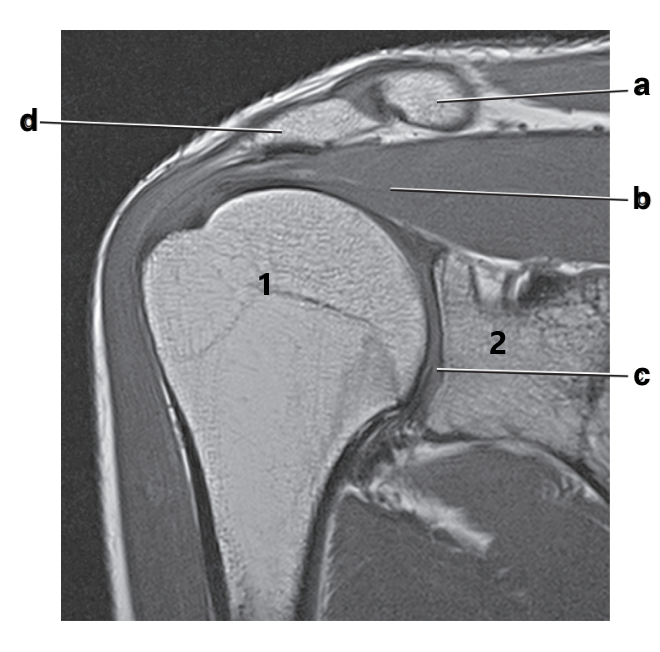

Acromion

Scapular spine

Supraspinatus tendon

Supraspinatus muscle

Superior glenoid labrum

Posterior glenoid labrum